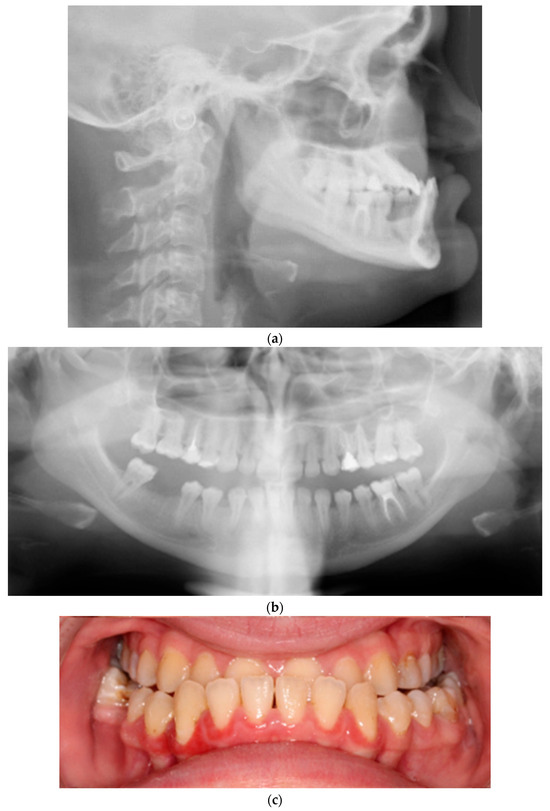

4.1. Osteogenesis Imperfecta: Orofacial Manifestations and Orthodontic Treatment

4.2. Dentinogenesis Imperfecta: Orοfacial Manifestations and Orthodontic Treatment